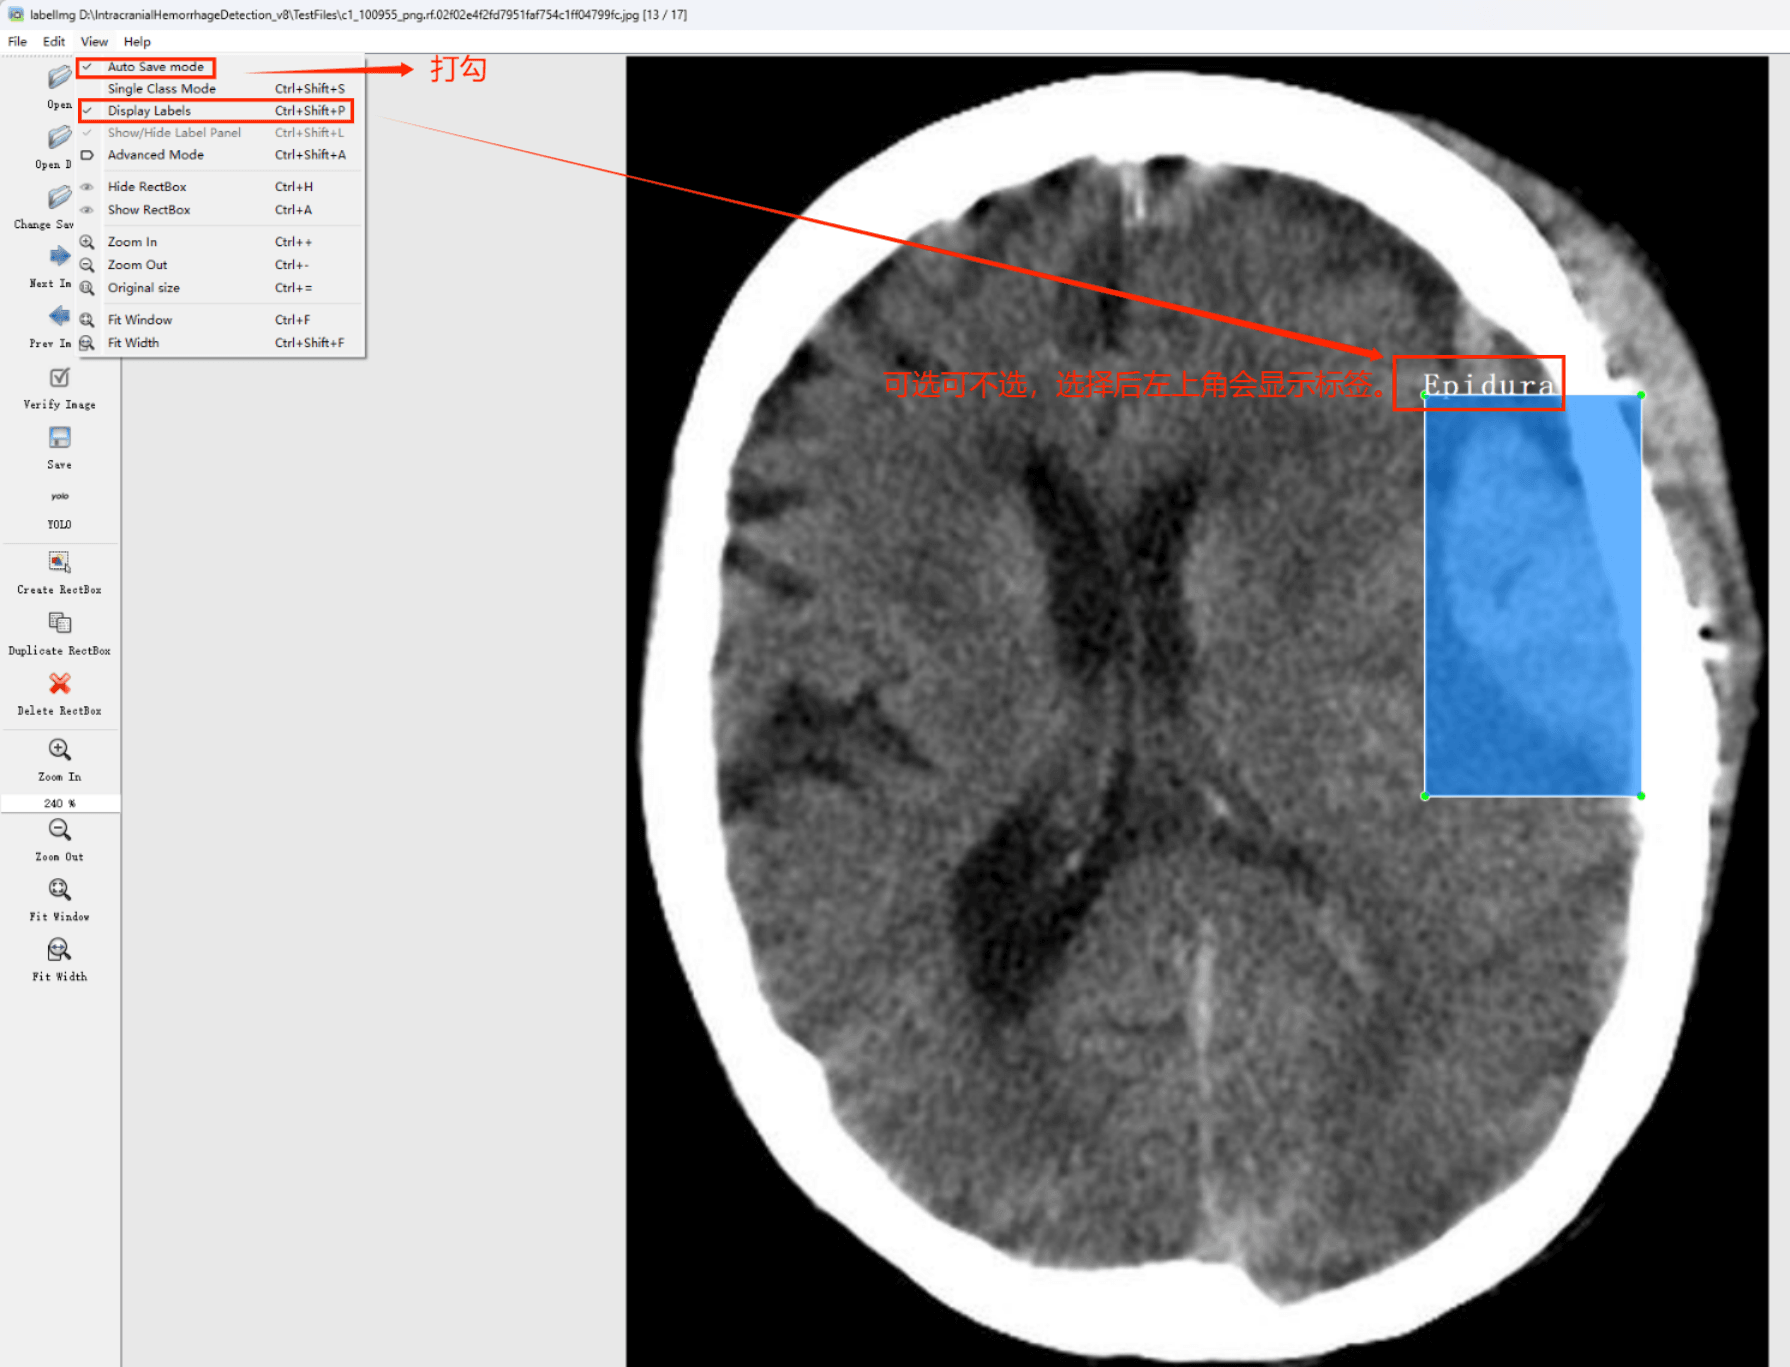

目标检测标注工具

(1)labelimg:开源的图像标注工具,标签可用于分类和目标检测,它是用python写的,并使用Qt作为其图形界面,简单好用(虽然是英文版的)。其注释以 PASCAL VOC格式保存为XML文件,这是ImageNet使用的格式。此外,它还支持 COCO数据集格式。

初识labelimg

打开后,我们自己设置一下

在View中勾选Auto Save mode

接下来我们打开需要标注的图片文件夹

并设置标注文件保存的目录(上图中的Change Save Dir)

接下来就开始标注,画框,标记目标的label,然后d切换到下一张继续标注,不断重复重复。